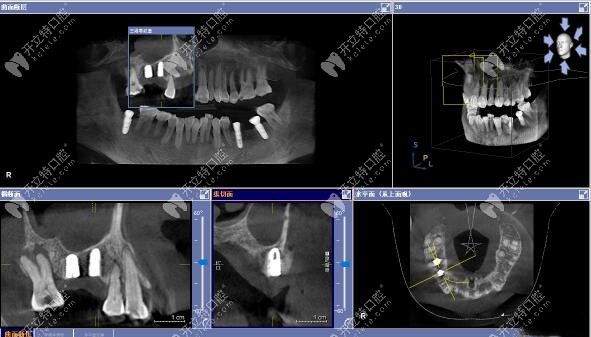

今日分享:用3D數(shù)字化導(dǎo)板技術(shù)做上頜竇區(qū)的精準(zhǔn)種植牙案例,植入的是美國皓圣3508和4507型號的種植體。

上頜竇區(qū)種植手術(shù)方案:利用3D數(shù)字化導(dǎo)板技術(shù),上頜15區(qū)缺牙位置種植皓圣3508植體+頰側(cè)GBR、上頜16區(qū)缺牙位置種植皓圣4507植體。

▲術(shù)后CT顯示:上頜15號、16號缺牙位置的植體,均已達(dá)到了預(yù)期位置。